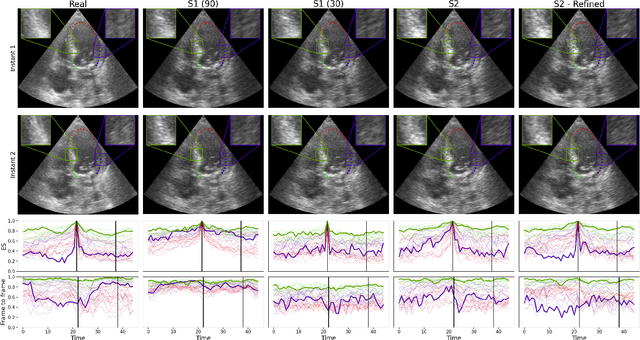

Abstract:Simulated ultrasound image sequences are key for training and validating machine learning algorithms for left ventricular strain estimation. Several simulation pipelines have been proposed to generate sequences with corresponding ground truth motion, but they suffer from limited realism as they do not consider speckle decorrelation. In this work, we address this limitation by proposing an improved simulation framework that explicitly accounts for speckle decorrelation. Our method builds on an existing ultrasound simulation pipeline by incorporating a dynamic model of speckle variation. Starting from real ultrasound sequences and myocardial segmentations, we generate meshes that guide image formation. Instead of applying a fixed ratio of myocardial and background scatterers, we introduce a coherence map that adapts locally over time. This map is derived from correlation values measured directly from the real ultrasound data, ensuring that simulated sequences capture the characteristic temporal changes observed in practice. We evaluated the realism of our approach using ultrasound data from 98 patients in the CAMUS database. Performance was assessed by comparing correlation curves from real and simulated images. The proposed method achieved lower mean absolute error compared to the baseline pipeline, indicating that it more faithfully reproduces the decorrelation behavior seen in clinical data.